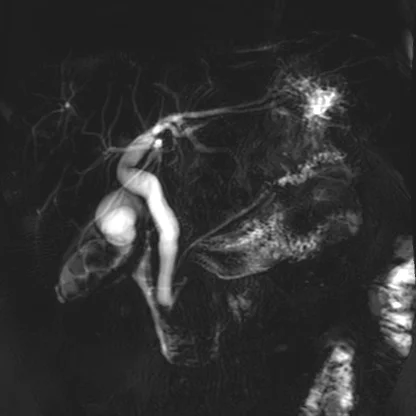

MRCP with focal ductal dilatation in the pancreatic tail shown very nicely